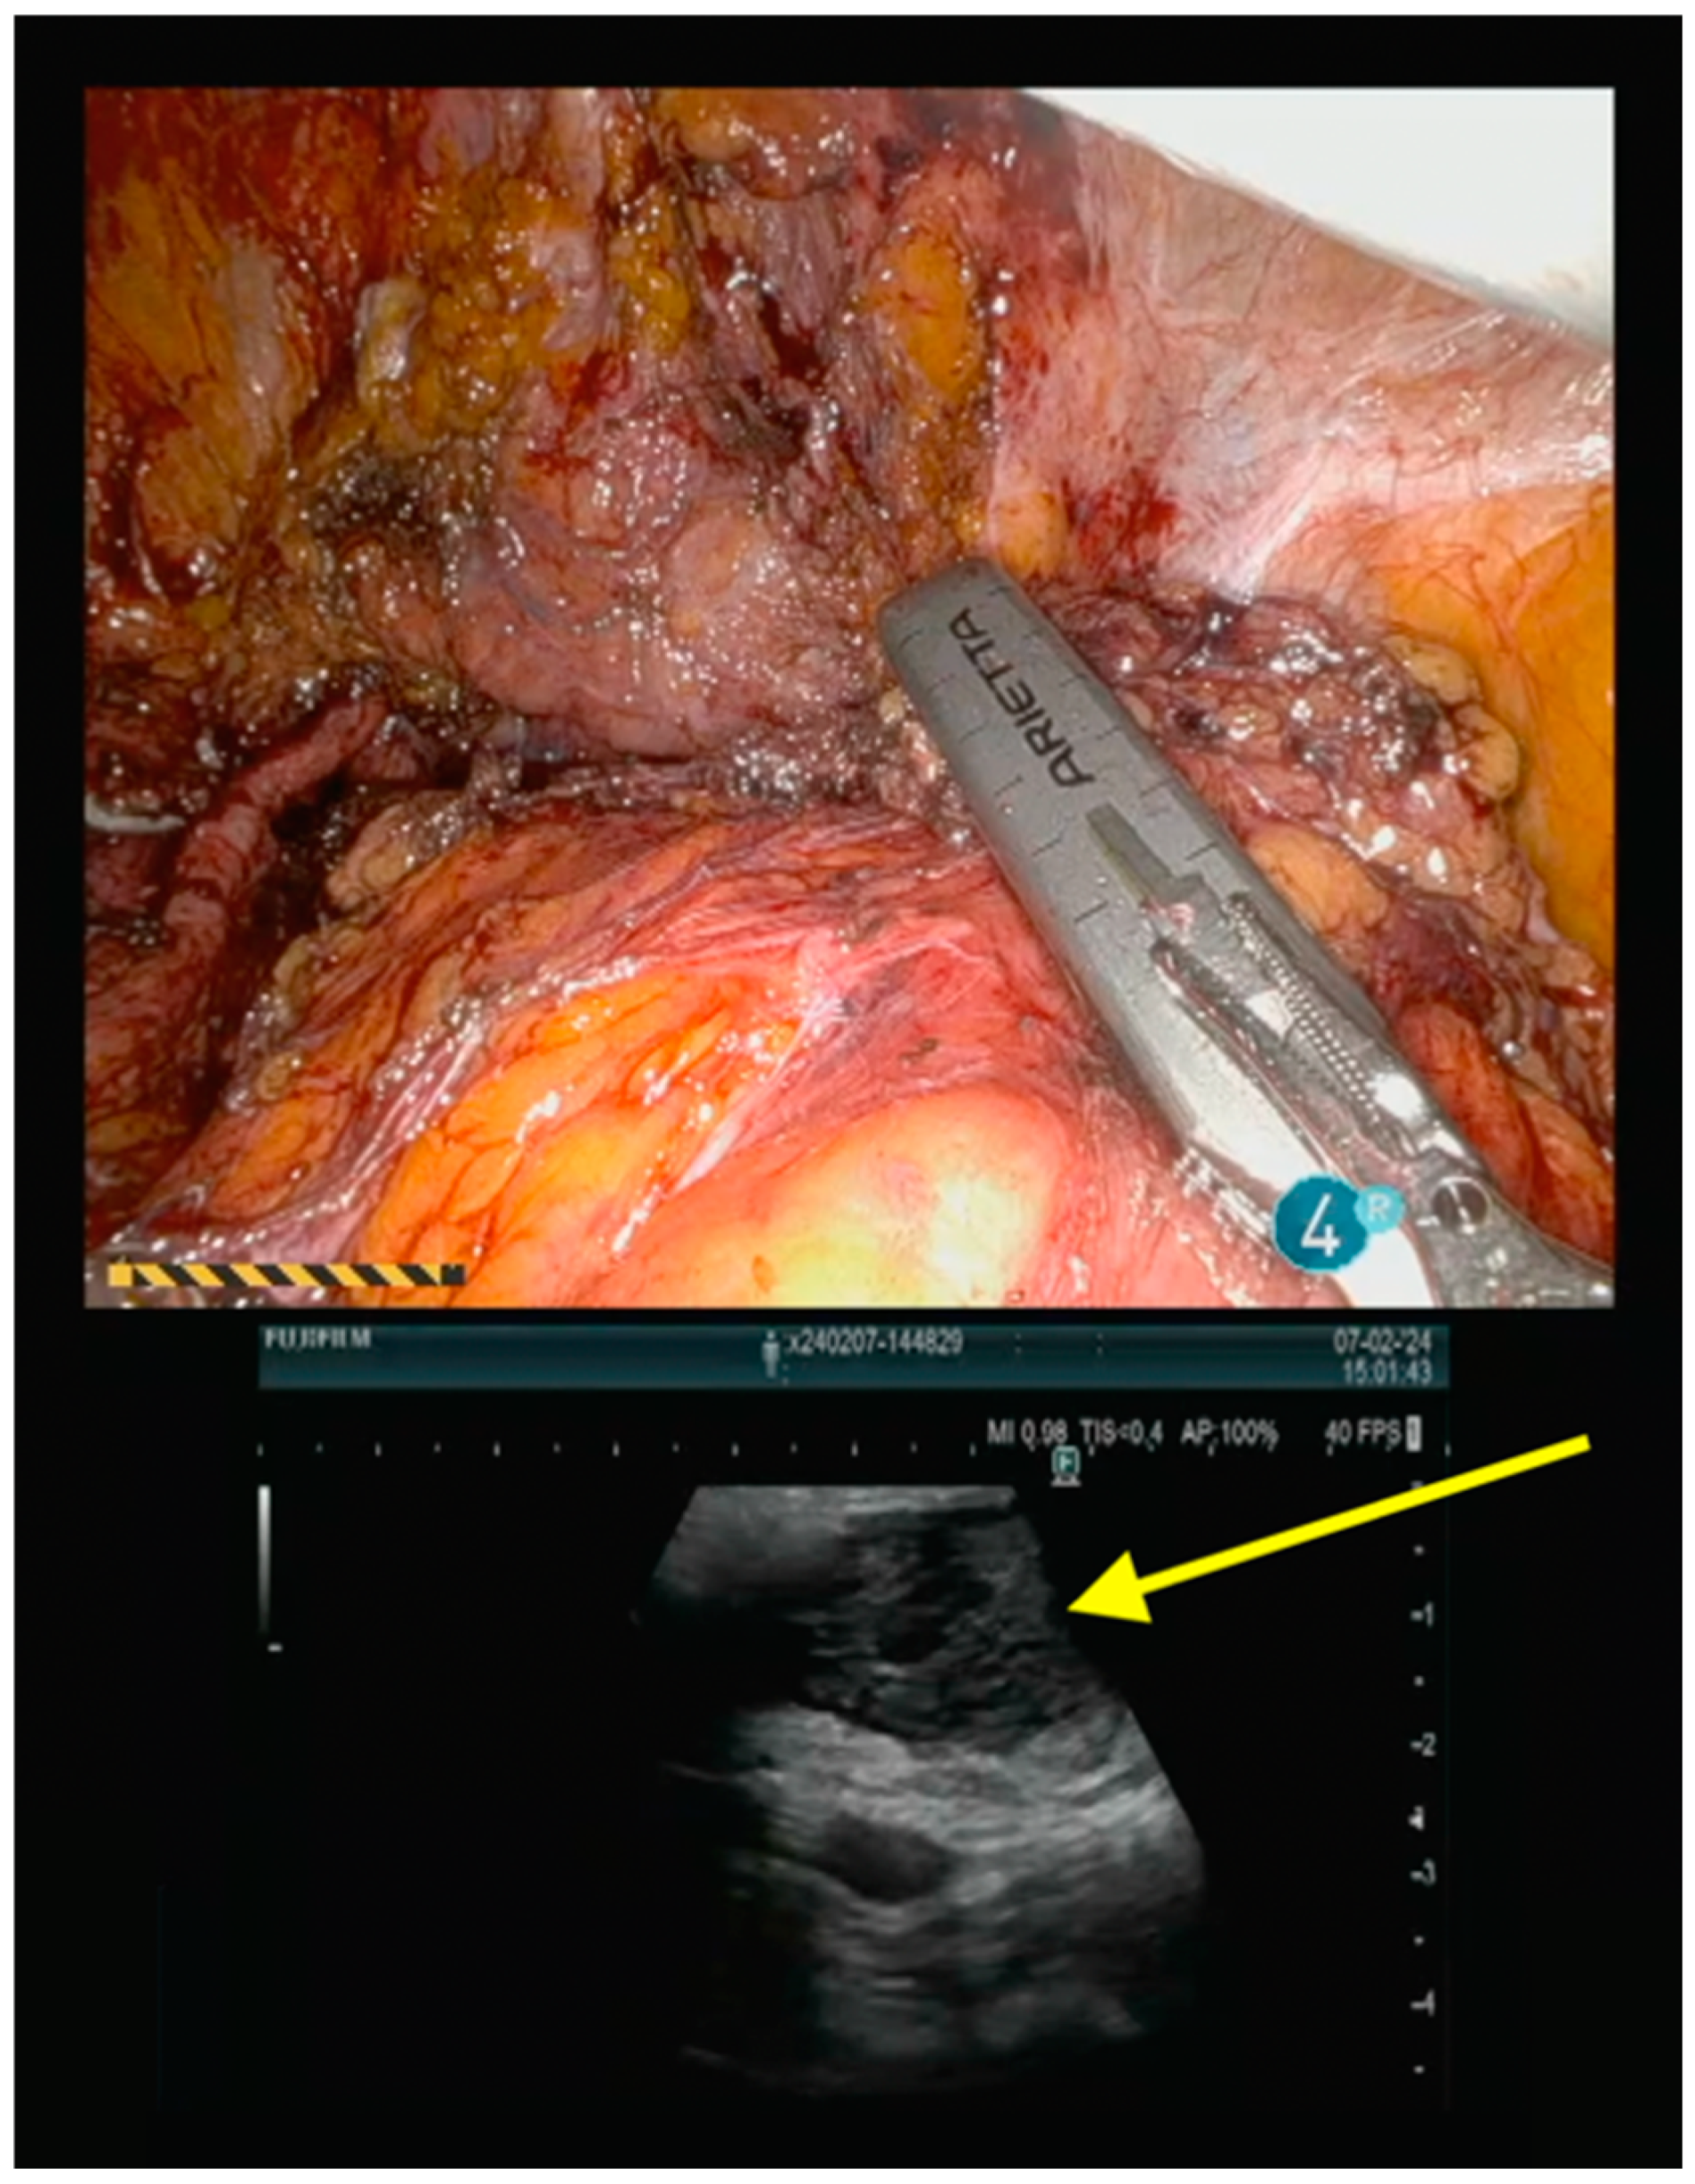

Operative Technique